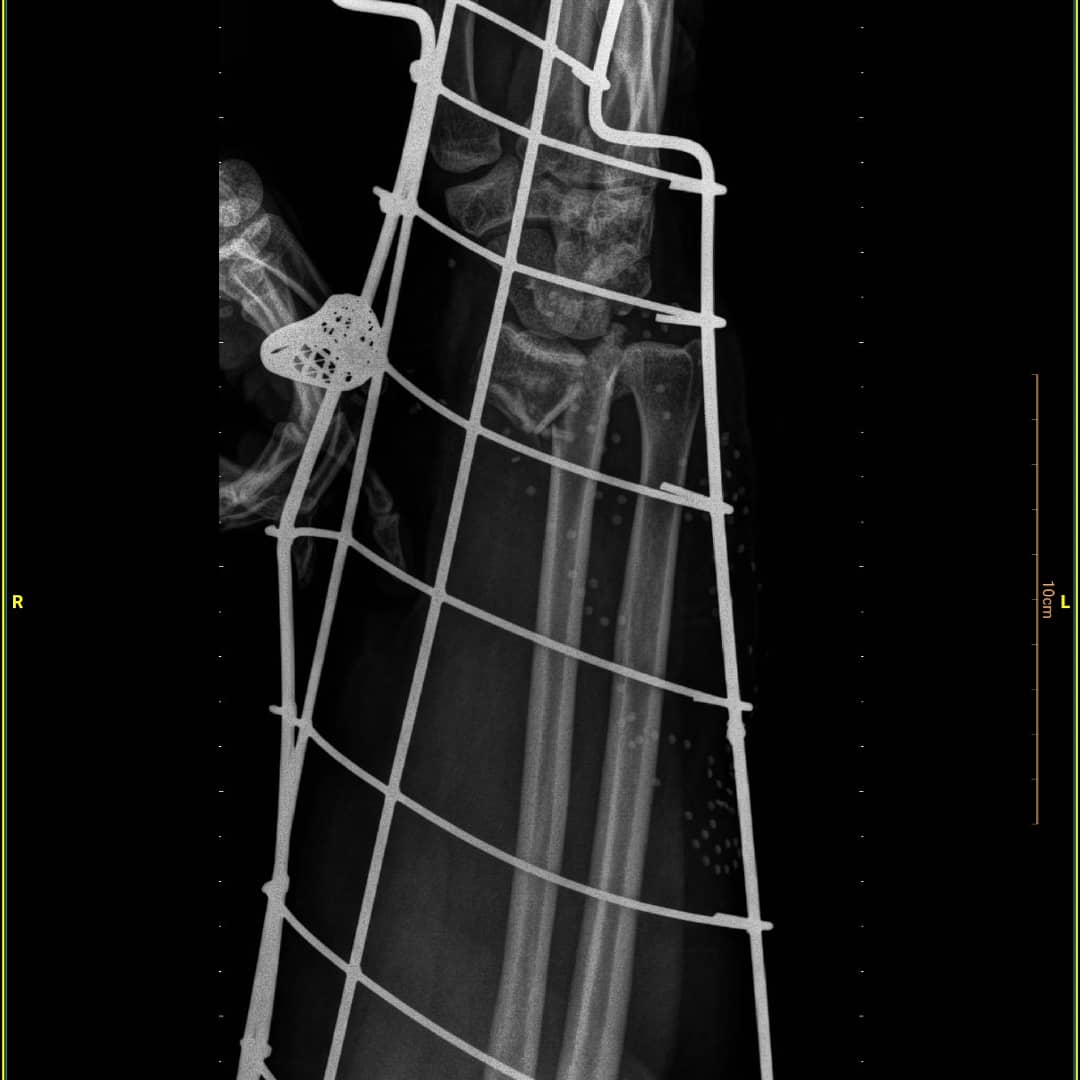

شکستگی خرد شده دیستال رادیوس و اسکافویید

خانم ۴۹ ساله که به دلیل واژگونی موتور چهارچرخ در ساحل انزلی، دچار شکستگی خرد شده مچ دست شده است. شکستگی دیستال رادیوس و اسکافویید و دررفتگی مفصل رادیواولنار به ترتیب فیکس شدند.